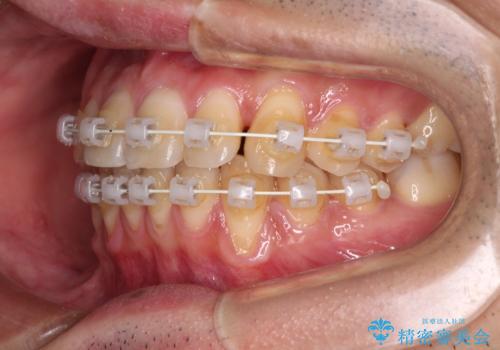

ワイヤー装置での上下前歯の部分矯正

- 矯正装置

- 審美装置

- 上下前歯のデコボコを気にして来院された患者様です。

口元の突出感や奥歯の咬み合わせに問題がなかったため、インビザラインの廉価版パッケージを用いるか上下ワイヤー装置での部分矯正を提案しました。

インビザライン廉価版パッケージの方が価格としては安価でしたが、日々の自己管理が煩雑であるとのことで、ワイヤー装置にて矯正治療を行うこととしました。

部分矯正は咬み合わせが不安定になったり、スペースができてしまったりと、適用となる患者様は極めて限られますが、こちらの方はスムーズに治療を終えることができました。